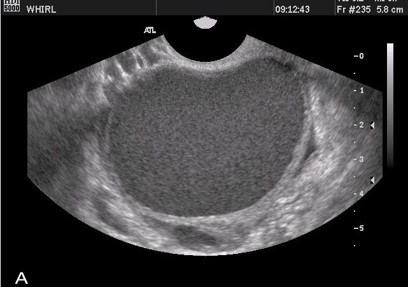

CHOCOLATE CYST

• Ovarian cysts containing brownish thick old blood that appears like melted chocolate.

• Found in patients with endometriosis